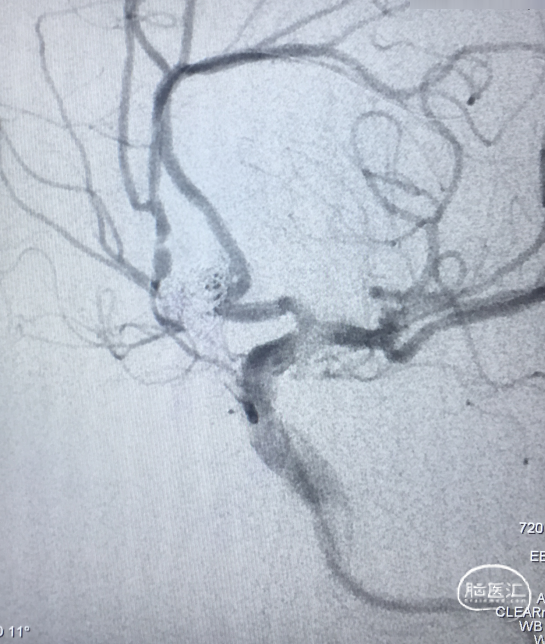

栓塞后即刻影像

工作角度造影显示动脉瘤栓塞致密,LACA A1、ACoA、双A2显影良好,左A2似有血栓(左图)。直头SL-10退至LACA A1末端,推注替罗非班1ml(右图)。

用药后再造影

再造影,发现RACA A2显影差,局部推注替洛非班无效,考虑前交通动脉血流受限,决定支架内球囊扩张。

术后影像

扩张术后造影:显示RACA血流恢复。

术后30分钟造影:LICA正侧位显示良好。

术后支架重建及蒙片:显示支架完全打开,贴壁充分,动脉瘤栓塞致密。